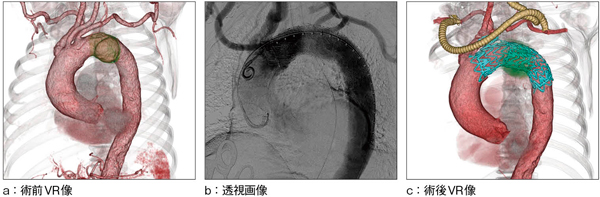

■症例1 debranched TEVAR(弓部分枝へのバイパスを伴う胸部大動脈ステントグラフト内挿術)

大動脈弓部のsaccular aneaurysm 56mmを指摘される。 左総頸動脈遮断。 両鎖骨下動脈バイパス-左総頸動脈バイパス形成(脳への血流を維持できるように右鎖骨下動脈から左総頸動脈のバイパス術施行)。 弓部にステントグラフト留置。 左鎖骨下動脈近位部をコイル塞栓。